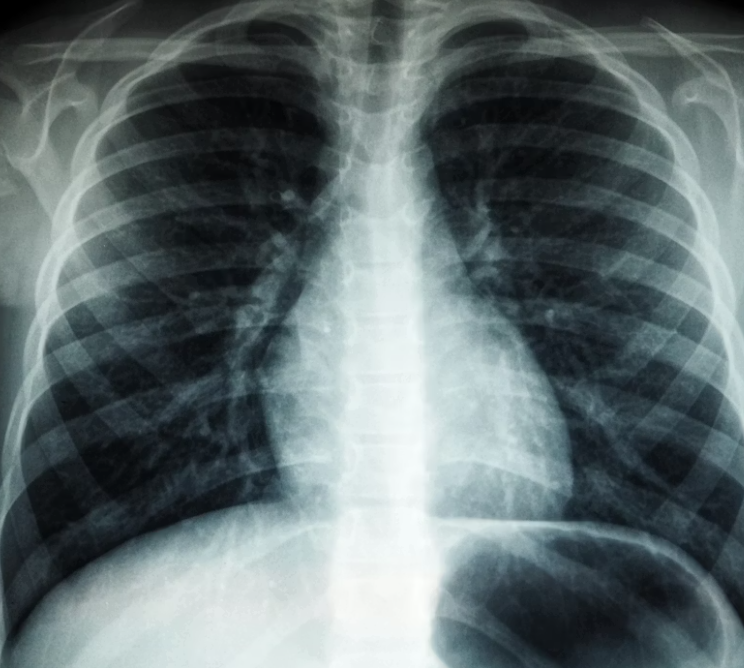

- 흉부 X-ray: 결핵성 의심 시 폐결핵 동시 확인